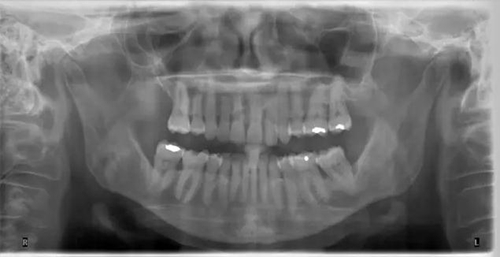

6.jpg

圖 6 全景片,清晰顯示關(guān)節(jié)。另外對牙列有大致概念,但對細(xì)節(jié),無法顯示得象根尖片或咬翼片那樣清晰(X 光片取自筆者治療過的病人)